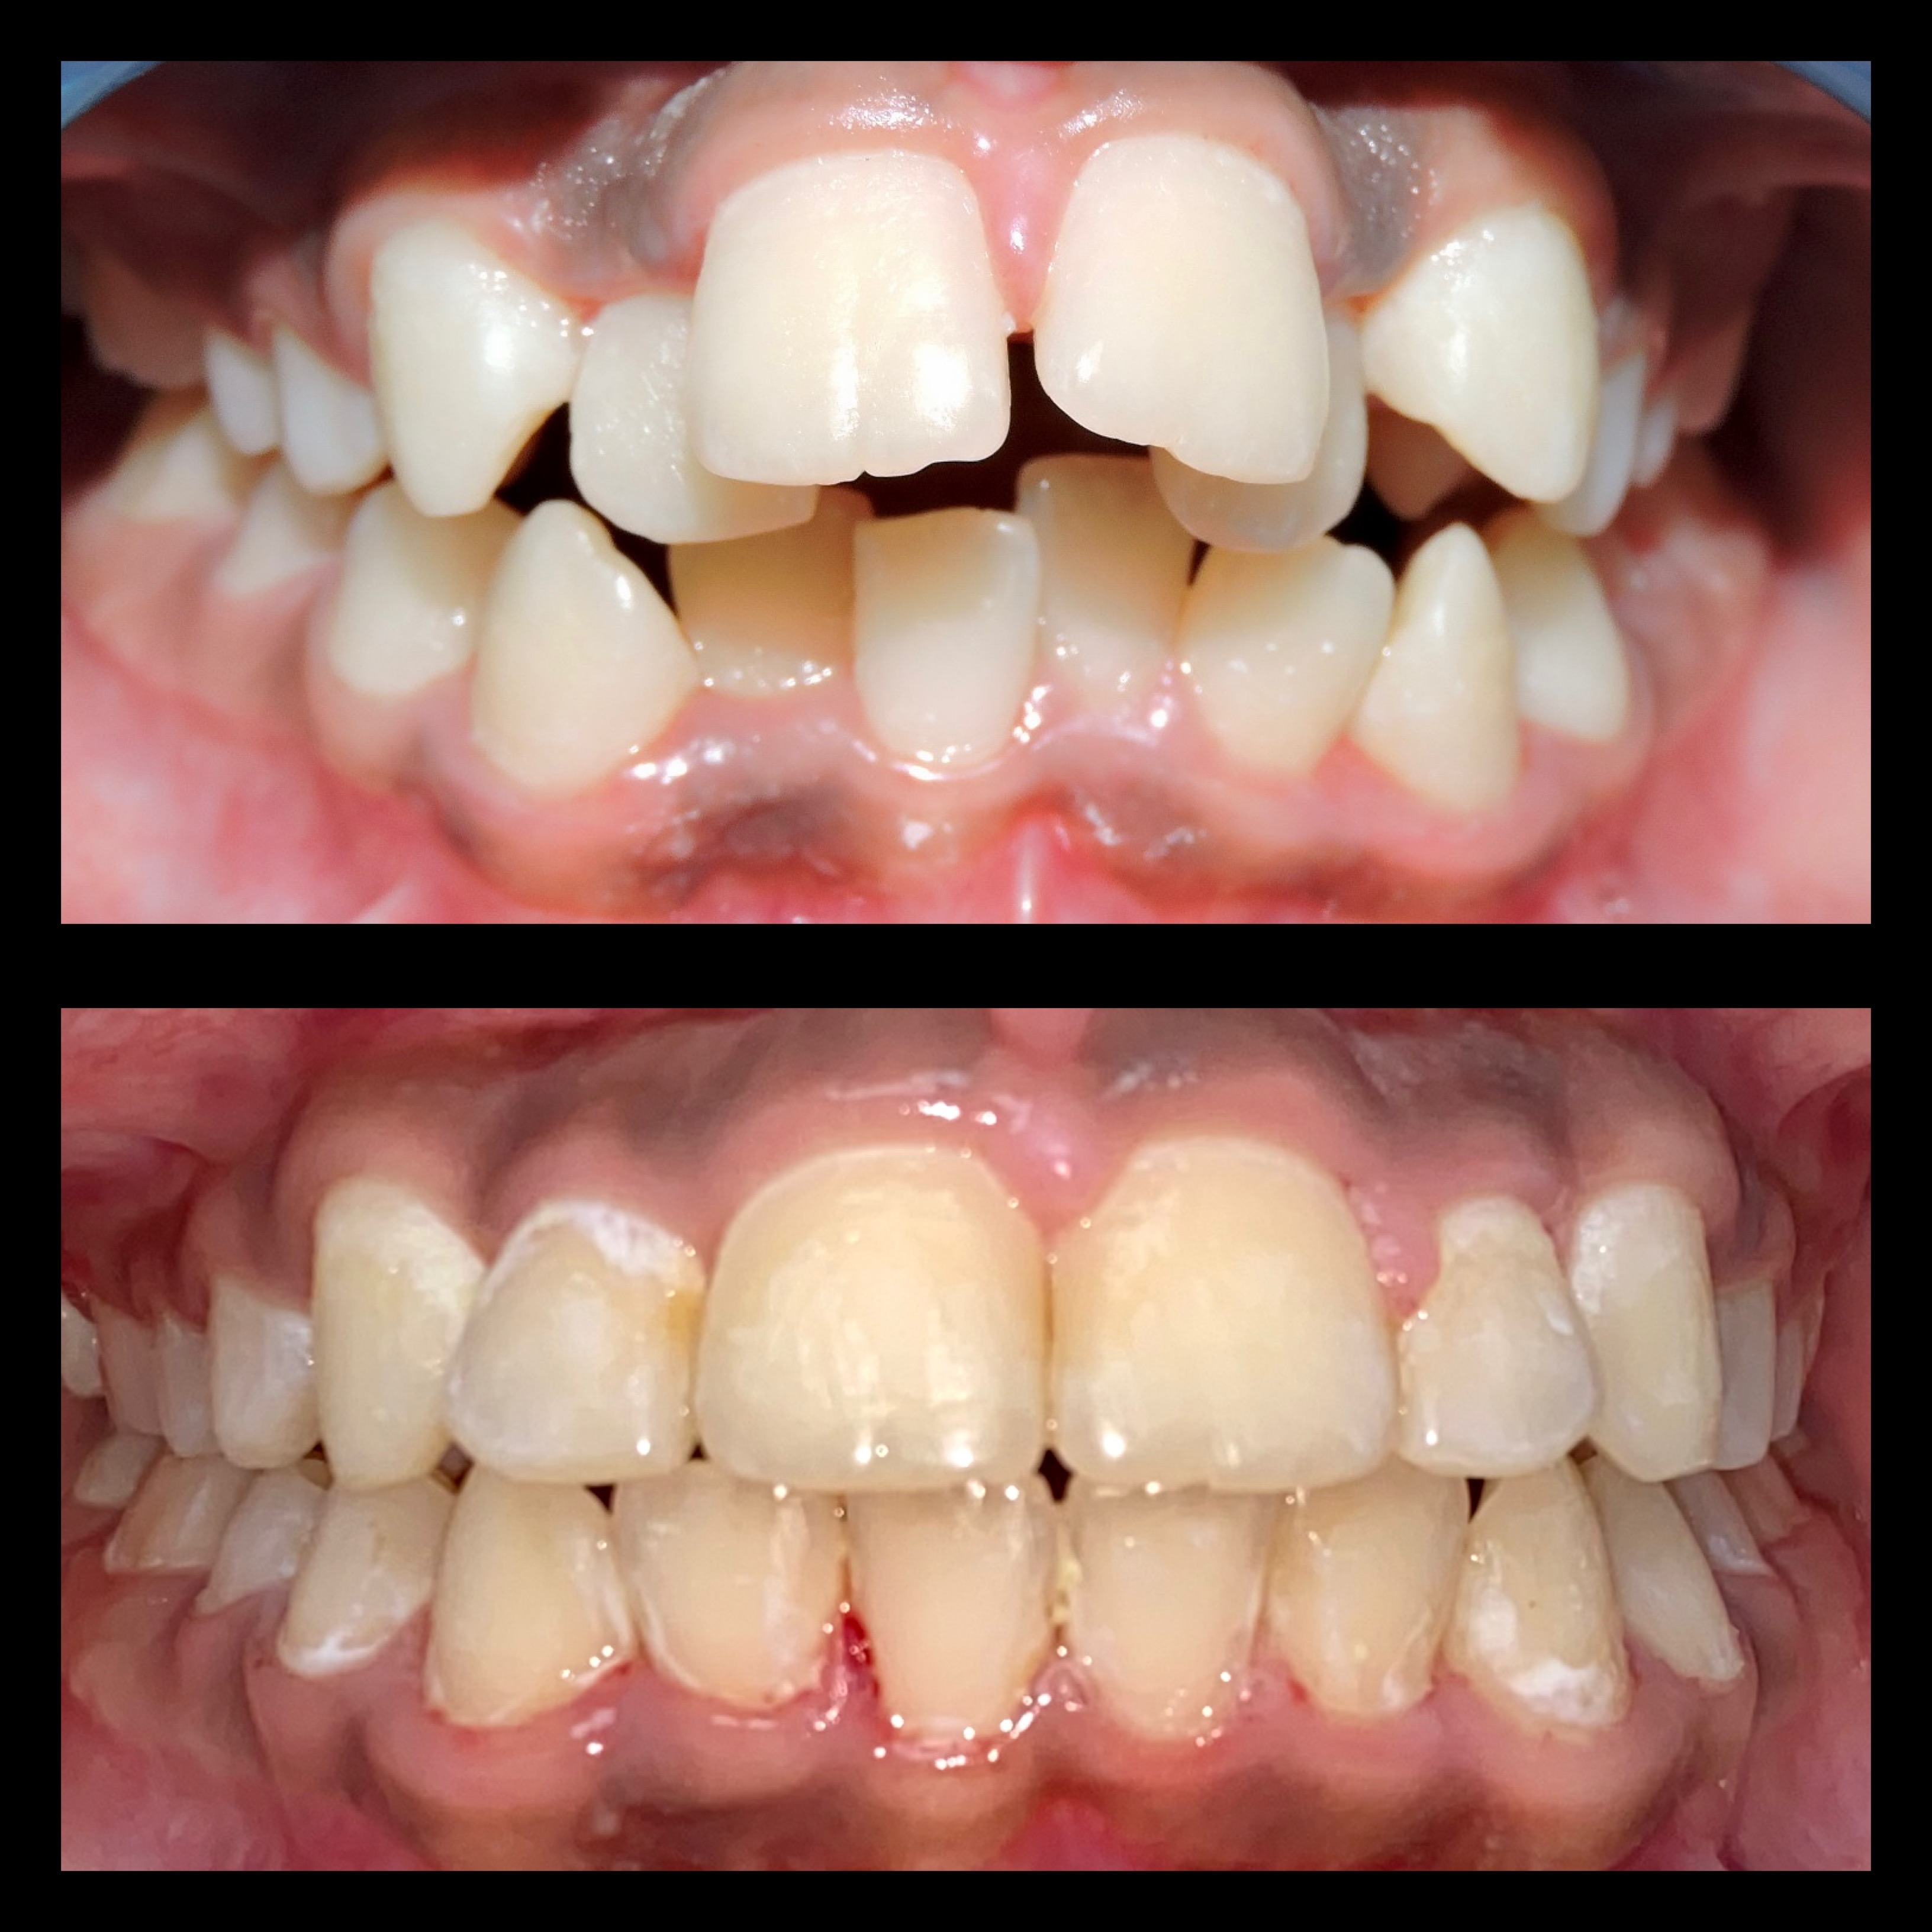

Gallery